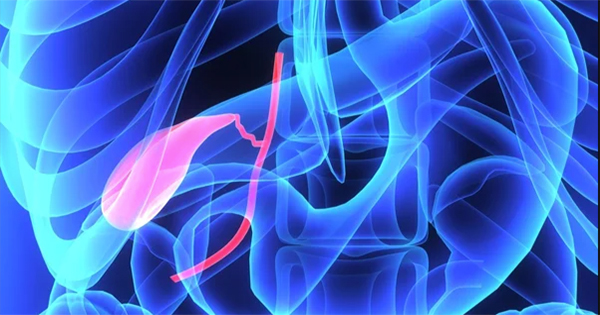

Una causa común de problemas en la vesícula biliar son los cálculos biliares, también conocidos como colelitiasis. Los cálculos pueden formarse cuando existe un desequilibrio en la composición de la bilis, como un exceso de colesterol o bilirrubina, o una deficiencia de sales biliares.

Los cálculos en la vesícula biliar son comunes y, por lo general, no causan problemas. Sin embargo, pueden obstruir el paso de la bilis hacia el intestino delgado, bloqueando la vesícula biliar o alojándose en los conductos biliares. Esto puede causar síntomas, sobre todo después de ingerir alimentos grasos. Las obstrucciones pueden provocar una inflamación grave de la vesícula biliar (colecistitis), que puede derivar en infección y pancreatitis.

Otros posibles problemas que pueden afectar la vesícula biliar incluyen los siguientes:

- Colecistitis alitiásica: Inflamación de la vesícula biliar no causada por cálculos biliares.

- Discinesia biliar: Dificultad para vaciar la vesícula biliar.

- Carcinoma de vesícula biliar: Cáncer de la vesícula biliar.